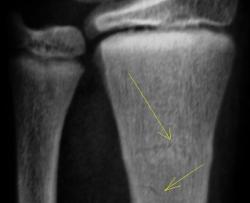

Дело в том, что в данном случае не одна а несколько линий перелома.

Кроме основного – "зеленая ветка" – другой недостоверен: может быть артефактом. На боковой рентгенограмме полоса слишком чёткая для нерезкого в целом снимка, похожа на полосы в области запястных костей. Там нет переломов? Подмигивает В прямой проекции обе линии принадлежат поднадкостничному перелому.